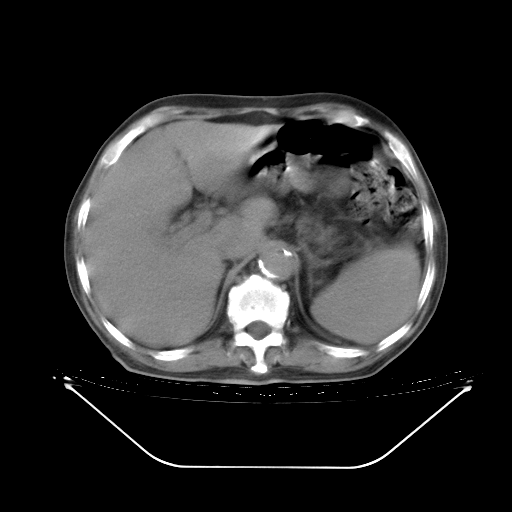

胸腹部CT,诊断意见:左上肺叶钙化灶、左侧胸膜局限性增厚并钙化、胆囊炎。描述部分肺组织呈磨玻璃样改变。

今天复查肺部CT,发现双肺广泛磨玻璃样改变。所以我把3月19日和5月9日相隔50天的肺部CT上传。请大家会诊。

5月9日肺部CT(在4月27日齐鲁医院肺部CT描述部分肺组织磨玻璃样改变,12天后肺组织广泛磨玻璃样改变)